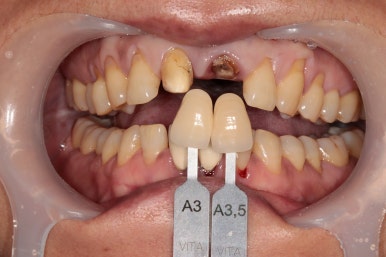

정밀 진단을 마친 후의 치료 계획은 다음과 같았습니다.

1. 뿌리만 남은 치아는 발치를 하고,

2. 양옆의 치아는 신경치료를 진행하고,

3. 지르코니아 보철물을 브릿지 형태로 수복한다.

환자분께 이러한 증상이 발생하게 된 배경부터,

치료 계획 및 과정을 꼼꼼하게 설명드리고 치료를 시작하였습니다.

부러진 뿌리 부분은 임플란트도 권해드렸으나.

환자분께서 아무래도 임플란트 수술은 피하고 싶다고 하셔서,

브릿지 형태로 수복하는 것으로 결정되었습니다.